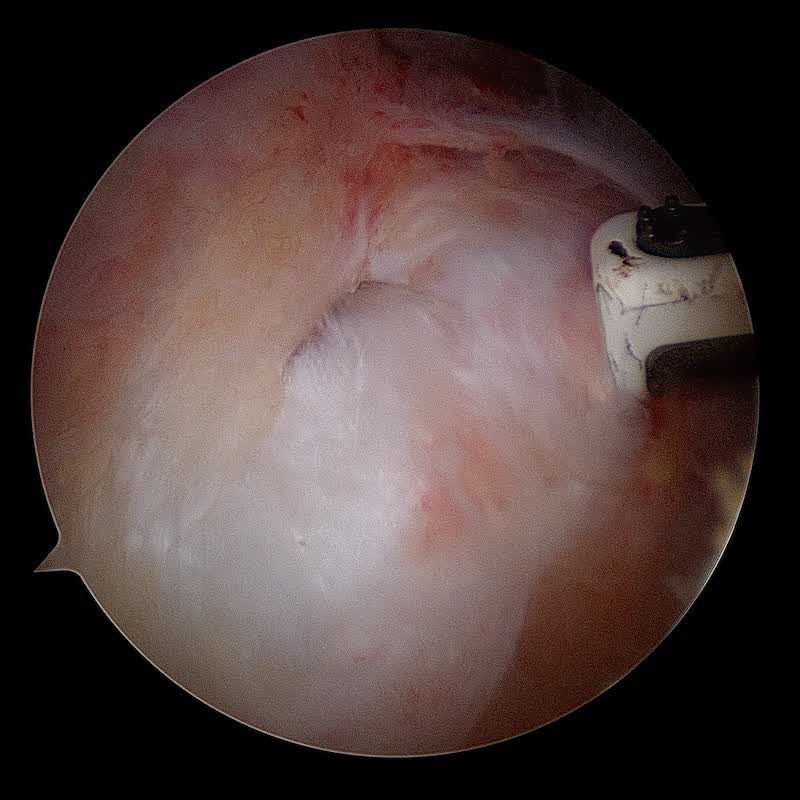

Le tendon est ensuite réparée après passage des sutures au travers du tendon. Une deuxième rangée d'ancres permet de plaquer le tendon contre l'os.

La cicatrisation tendineuse nécessite 6 à 8 semaines.